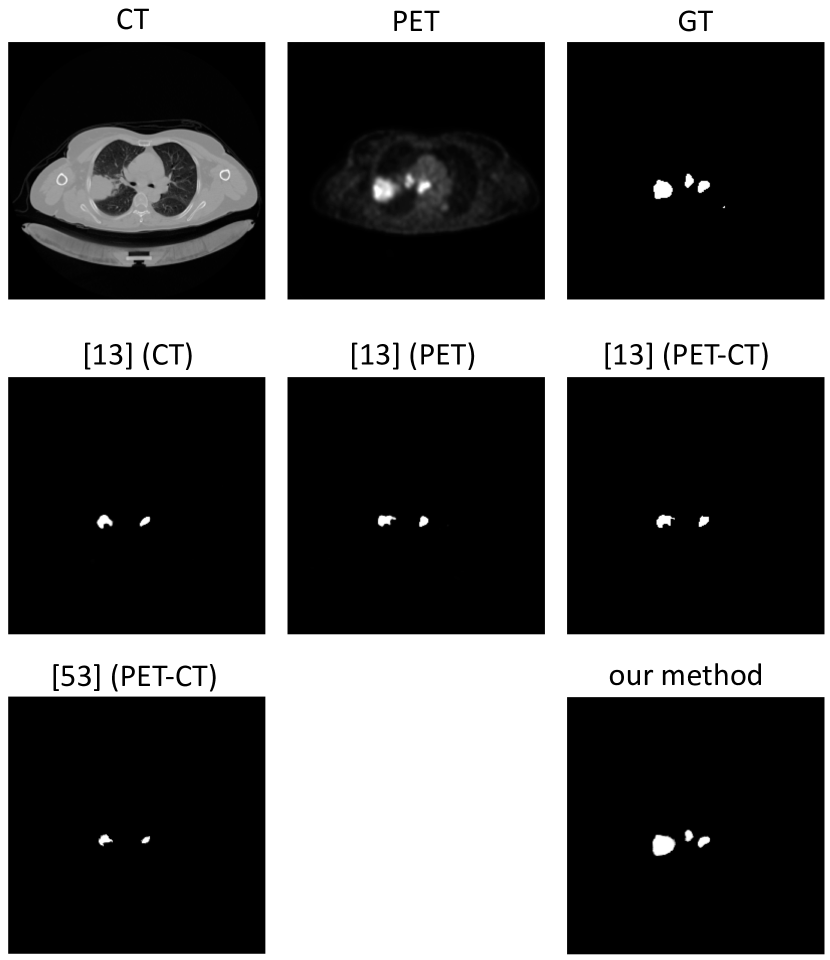

Table III is a comparison of the tumor segmentation performed by our co-learning CNN with two recently published PET-CT lung tumor segmentation techniques. The tumors segmented by our co-learning CNN have a significantly () higher Dice score that the baselines.

Fig. 6 is a visual comparison of the segmentation results for a PET-CT image slice with tumors within the lung field as well as in the mediastinum; a larger version is included as Fig. S4 in the Supplementary Materials. The figure shows that our method was able to segment three tumors in different locations across the slice, although they are all slightly over-segmented relative to the GT. In contrast, baseline methods had a tendency to under-segment the tumors.

Our method has a significantly higher Dice score () than the baseline tumor segmentation methods [13, 53]. The baseline methods produced lower Dice scores when using slices as inputs compared to using patches as inputs. The reason for this outcome is that like other recent PET-CT lung tumor segmentation techniques [51, 54], the baselines were designed for inputs where the tumors were cropped from the full image and centered within an image patch. The results indicate that it is likely that the baselines were unable to identify the tumors when the image contained more varied anatomical and functional information from the full image slice, such as with tumors outside the lung fields (e.g., poor segmentation of tumors in the mediastinum or hilar nodes in Fig.6). Our CNN had a comparable Dice score to the co-segmentation baseline [13] with PET-CT patch inputs, which suggests that our CNN does not rely upon cropped data to learn. The overall lower Dice scores when compared to the baseline publications (which reported scores of about 80%) is primarily attributed to the difficulty of automatically segmenting images with hilar (Stage II) and mediastinal (Stage III) nodal involvement, which is more challenging than segmenting tumors within the lung field. We note that other methods in the literature that are capable of segmenting tumors across the entire image are not automated and require human input to define the tumor bounding box or seed points for initial segmentation [17, 28].

The co-segmentation baseline [13] follows a similar approach to the MB fusion baseline; the individual modalities are processed separately and the predicted regions can then be merged. Fig. 6 shows that the CT image alone is insufficient to identify all the tumors within the image: the heterogeneous tumor within the lung is under-segmented while one of the two mediastinal tumors was not segmented. The PET segmentation detects three tumors but only the regions with the highest SUV have been detected leading to under-segmentation. The integration of the PET and CT result obtains an appropriate ROI for the primary tumor, but the disease outside the lung fields are not well-defined. The variational baseline [53] relies upon the initial segmentation of the CT image with refinement of the boundaries via PET. However, the CT image is insufficient for the mediastinal tumour segmentation, resulting in poor overall segmentation performance.

In comparison to the baselines, our CNN was able to identify and segment tumors consistently from the full PET-CT image slice. This outcome was due to its ability to consider PET and CT information in an integrated manner, with the fusion maps balancing the modality-specific information. The results indicate that our method is capable of segmenting tumors across different anatomical locations without prior cropping of patches around the tumor region.